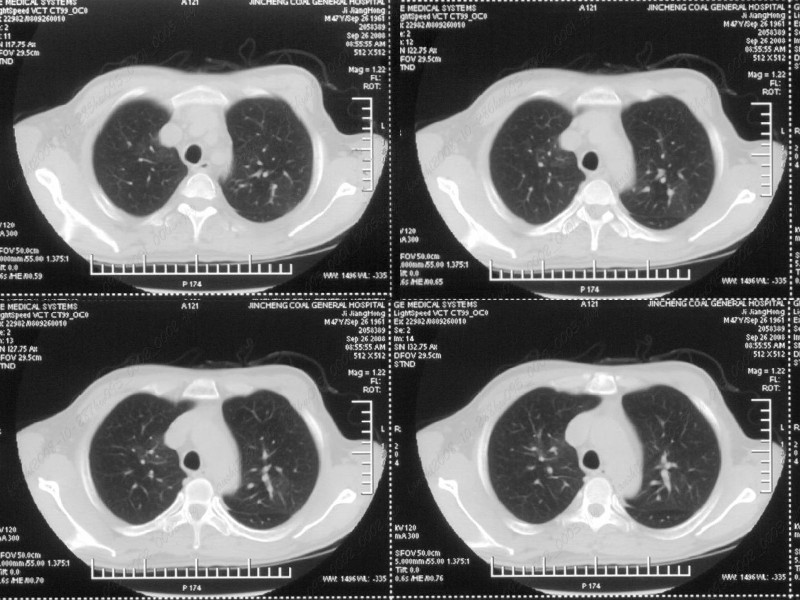

男性,47岁。胸部不适一年,ct检查发现右胸膜下结节。http://www.radida.com/bbs/forum.php?mod=viewthread&tid=46094

病灶周围似有纤维化征像,增强明显强化,但中央可见点状低强化区,考虑慢性病变可能如炎性假瘤等,病灶边缘部分毛糙有切迹,双侧胸腔少量积液影,不除外恶性

结节未见明显强化,局部胸膜增后粘连,内缘纹理影增重伴小围星灶,局部胸膜下小三角状实变影,尖端见纤维索牵扯征,综合考虑炎性病变,有增殖表现,不出外tb灶

右肺中叶外侧段胸膜下结节状病灶,性质待定(不排除周围型肺癌可能)。

右前胸膜下小结节,边缘有小纤维条索影与胸膜粘连,考虑如炎性假瘤之类慢性病变可能。期待二周后的结果。

小结节的周围似乎与斜裂的走行有关,边缘分界不很清楚,与侧胸膜关系密切,有轻度强化,不能除外恶性,建议密切观察。

汇报临床诊断:右肺动脉分枝栓塞

右肺静脉充盈缺损,左心房体积小,右肺动脉远端动脉充盈缺损,右肺血管影细小,考虑;右肺动脉远端栓塞.